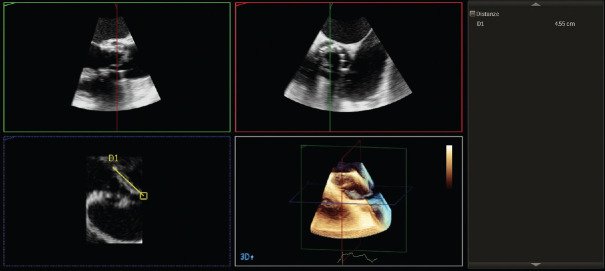

感染性心内膜炎(IE)的诊断基于临床怀疑,并辅以一致的微生物学和仪器数据。心脏瓣膜(原生瓣膜或人工瓣膜)或人工心内膜受累的证据是 IE 的主要诊断标准。经胸超声心动图(TTE)是初步诊断的首选技术,而经食道超声心动图(TEE)则推荐用于 TTE 未确诊或阴性的患者、高度怀疑 IE 的患者以及 TTE 阳性的患者,以记录局部并发症。在对无并发症的 IE 进行随访时,应考虑重复 TTE 和/或 TEE,以检测新的无声并发症并监测植被的大小。在 IE 的情况下,三维(3D)TEE 的作用越来越大;事实上,这种技术也被证明有助于诊断 IE 及其并发症,因为它可以获得无限平面和容积重建。在这篇综述中,我们将介绍三维 TEE 的实用性及其在 IE 治疗中的附加值。

Infective endocarditis (IE) diagnosis is based on a clinical suspicion supported by consistent microbiological and instrumental data. Evidence of involvement of cardiac valves (native or prosthetic) or prosthetic intracardiac material is a major diagnostic criterion of IE. Transthoracic echocardiography (TTE) is the initial technique of choice for the diagnosis while transesophageal echocardiography (TEE) is recommended in patients with an inconclusive or negative TTE, in patients with high suspicion of IE, as well as in patients with a positive TTE, in order to document local complications. Repeating TTE and/or TEE should be considered during follow-up of uncomplicated IE, in order to detect new silent complications and monitor vegetation size. In the setting of IE, the role of three-dimensional (3D) TEE is increasing; in fact, this technique has also been shown to be useful for the diagnosis of IE and its complications as it allows to obtain infinite planes and volumetric reconstructions. In this review, we will describe the usefulness of 3D-TEE and its added value in the management of IE.